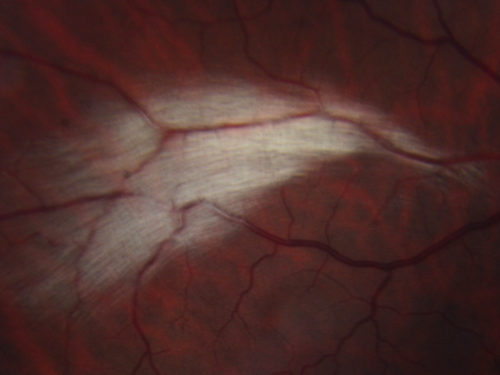

Myelinated Nerve Fiber Layer Right Eye (white area)

62-year-old man myelinated nerve fiber layer in the right eye. OD 20/25, OS 20/30.